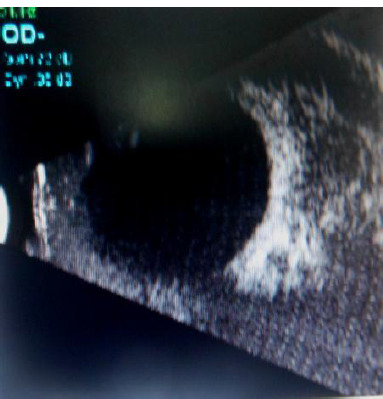

Orbital pseudotumor is nonspecific orbital inflammation (NSOI). It is a benign, non-infectious, space-occupying inflammatory lesion of the orbit. NSOI can affect various tissues in the orbit, such as the lacrimal gland and extraocular muscles. The most common classification is based on clinical presentation. Bacteria, viruses, fungi, or parasites can cause infectious orbital inflammation. It is a diagnosis of exclusion after ruling out inflammatory, infectious, and neoplastic causes. We present a case of a male in his sixties who presented with progressive pain, swelling, blurry vision, and forward protrusion of his right eye. He had no history of trauma or recent illness. His general physical and systemic examination was within normal limits. His ocular examination showed eyelid edema, erythema, eccentric proptosis, and a mature cataract in his right eye. His left eye showed a lenticular opacity. CT orbit revealed a homogenous isodense lesion observed without any globe distortion. A diagnosis of orbital pseudotumor was made. The patient was treated with oral corticosteroids, and an excision biopsy was done, resulting in symptomatic improvement and regression of inflammation at follow-up. In complex cases of inflammatory orbital pseudotumor, particularly those with granulomatous inflammation, some initial success has occurred with monoclonal antibodies against tumor necrosis factor (TNF)-alpha or with lymphocyte depletion using rituximab. Our patient, however, responded well to an excision biopsy and a course of oral steroids.